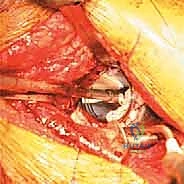

3. إزالة المفصل القديم والأسمنت (Implant Removal)

هذه من أخطر المراحل. يجب إزالة الكوب القديم، والبراغي، والأسمنت الطبي بدقة وحذر شديدين لتجنب إحداث المزيد من الدمار في العظم المتبقي أو إصابة الأوعية الدموية المجاورة. يستخدم الدكتور هطيف أدوات دقيقة متخصصة (مثل الأزاميل المرنة والمناشير الدقيقة) لفصل المفصل عن العظم.

4. تنظيف العيب العظمي وتحضيره (Debridement)

بعد إزالة المفصل، يظهر حجم الكارثة العظمية. يقوم الجراح بتنظيف التجويف الحقي من جميع الأنسجة الليفية، والندبات، وبقايا البلاستيك والمعدن، والعظم الميت. الهدف هو الوصول إلى عظم حي ينزف دماً، وهو شرط أساسي لنجاح الترقيع العظمي.